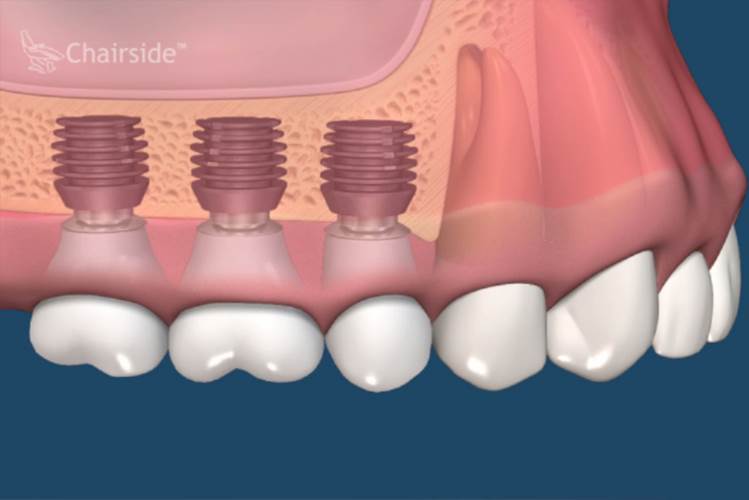

All-on-Fou/Six

近年來由於人工植牙的技術普及,患者大都知道植牙可做固定式假牙,但同樣的有時患者因為身體、經劑因素等受限,也可以考慮植入幾支人工植牙,再完成固定可撤式活動義齒,這樣可讓活動式假牙的固定性有效加強。通常上顎可用6支植體,下顎則4-5支植體固定,如需更穩定的受力,亦可再增加植體數目。(圖52-55)

圖52

圖53

圖54

圖55

參考病例: 固定式植牙牙橋&固定可撤式活動義齒